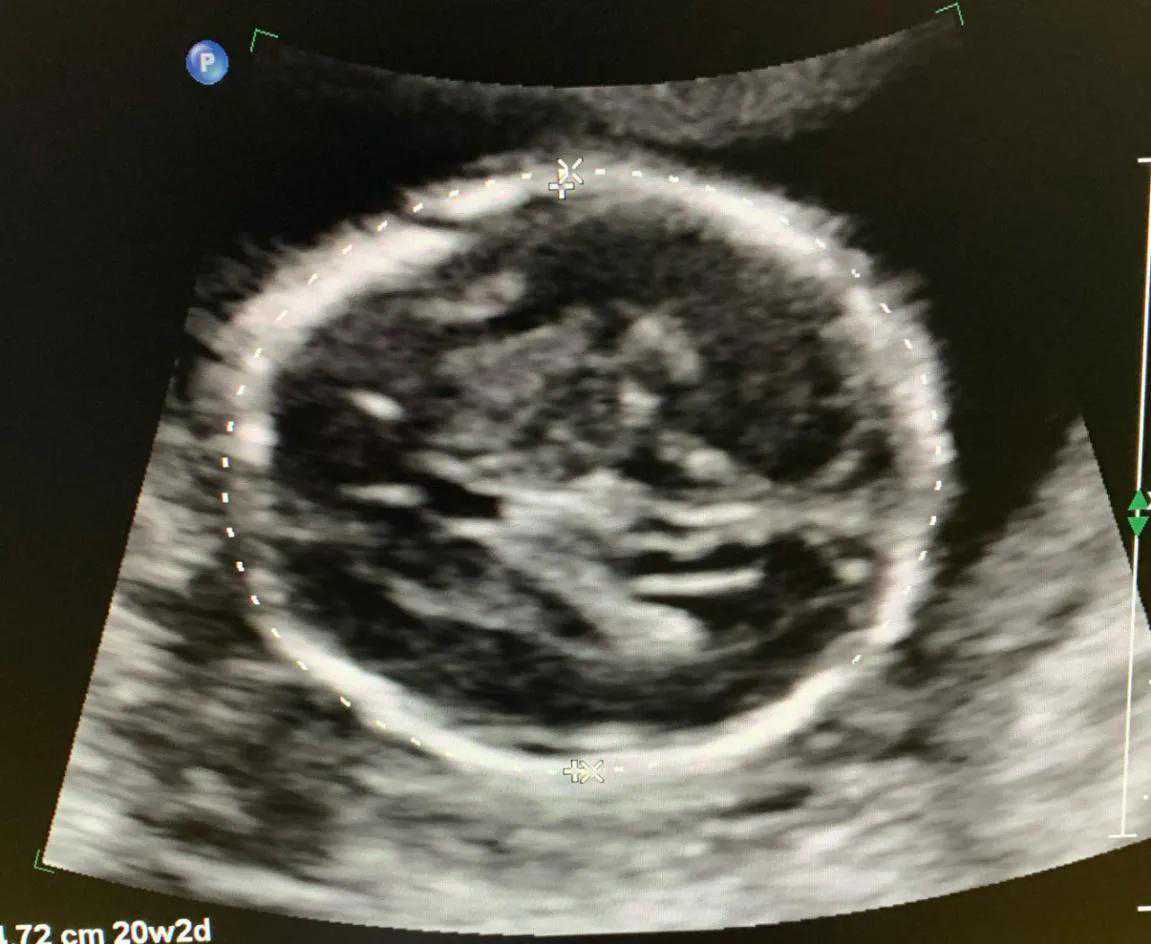

第三次超声检查孕20-24周,检查项目:产前诊断三级筛查,俗称大畸形筛查,也叫大排畸。主要为检查胎儿是否患有重大结构畸形,可以排除胎儿大的结构畸形,如无脑儿、脑膨出、胸腹壁缺损内脏外翻、单心腔、致死性软骨发育不良、严重的脊柱裂等。耗时较长,当胎儿体位不佳时,需要适当走动再次检查。

注意事项:三维、四维不是产前III级筛查必须检查。我们的大排畸超声,不是用三维四维来进行诊断和观察的,就像照相馆,你可以看到你认识的照片,但是摄影师不会也不可能告诉你,照片中的人是否得病了一样,三维是给您能看得懂的表面照片,不能穿透性的看到胎儿内部结构。所以,您在做排畸的时候,屏幕上显示的图(比如图3,就是排畸时候的胎儿头颅的图像),可能您都看不懂。

图3胎儿结构畸形筛查时头颅双顶径切面图